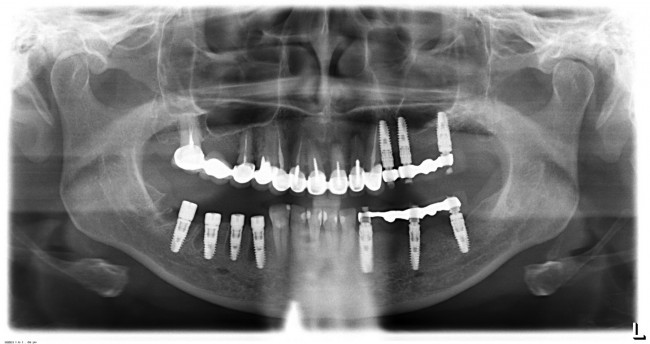

Вторая операция заняла чуть больше времени (90 минут), поскольку потребовалось удаление ретинированного зуба мудрости и синуслифтинг. Послеоперационные явления более выраженные — отек держался в течение нескольких дней, болезненных ощущений почти не было.

Стоит ли сейчас приступать к третьему и четвертому этапам, а именно — к удалению зубов и имплантации на правой стороне? На мой взгляд, нет. И тут срабатывает принцип, поспешишь — людей насмешишь. Ну подумайте сами — у пациентки не интегрированы импланты с левой стороны, вся жевательная нагрузка приходится на правую сторону. Удалив зубы, мы сильно увеличим нагрузку на оставшиеся передние сегменты, которые, если честно, находятся не в лучшем состоянии. И это не говоря о том, как пациентка будет себя чувствовать, не имея возможности нормально пережевывать пищу. Поэтому в наших интересах — дождаться интеграции имплантов слева, установить на них временные протезы, перенести на них жевательную нагрузку, и только потом приступать к работе на правой стороне.

И тут пациентка сказала: «Постойте! У меня так легко проходят операции, так почему бы нам не поставить большее количество имплантов в правой части? В идеале, чтобы каждая коронка опиралась на свой имплантат — я больше не хочу мостовидные протезы!» Желание пациента — закон. Поэтому на правой стороне мы усложняем работу:

Как вы думаете, сколько времени заняла третья хирургическая операция? 60 минут! Легко, быстро и комфортно. А главное — результативно!

В дальнейшем, после протезирования нижнего правого сегмента, мы, скорее всего, вернемся в левую часть и реализуем схему «одна коронка-один имплантат», поскольку это дает лучшие в эстетическом и функциональном отношении результаты. Ну и, пациентка так захотела.

Что в итоге получилось? Пока три этапа, по 60-90 минут каждый. Минимум времени операции, минимум травмы. Как результат — успешное комфортное лечение с высокой эффективностью и без больших единовременных затрат. Это всяко лучше, чем одна многочасовая дорогостоящая операция с тяжелым послеоперационным периодом и существенным дискомфортом. Вот вы бы что выбрали?